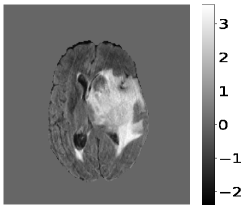

The pre-processing steps on the input MR image and target images are pre-requisites before training the deep learning model. Z-score normalization scales the pixel intensity values of the input MR image to have a mean of zero and a standard deviation of one, and is shown in Figure 2. It is a standard technique in medical imaging to account for variations in image acquisition parameters and to ensure consistent pixel intensity values across different images. The z-score normalization is applied only to brain tissue regions in the MR images, the rest remain unchanged.

The target images have been converted into one-hot vectors. It encodes the segmentation labels as binary vectors, with each dimension corresponding to a distinct label, Edema, NET/NCR, or ET. The normalized input MR images are then stacked. The ground truth and the corresponding one-hot vectors are shown in Figure 3. These pre-processing steps ensure that the input data is in a suitable format for training the deep learning model.